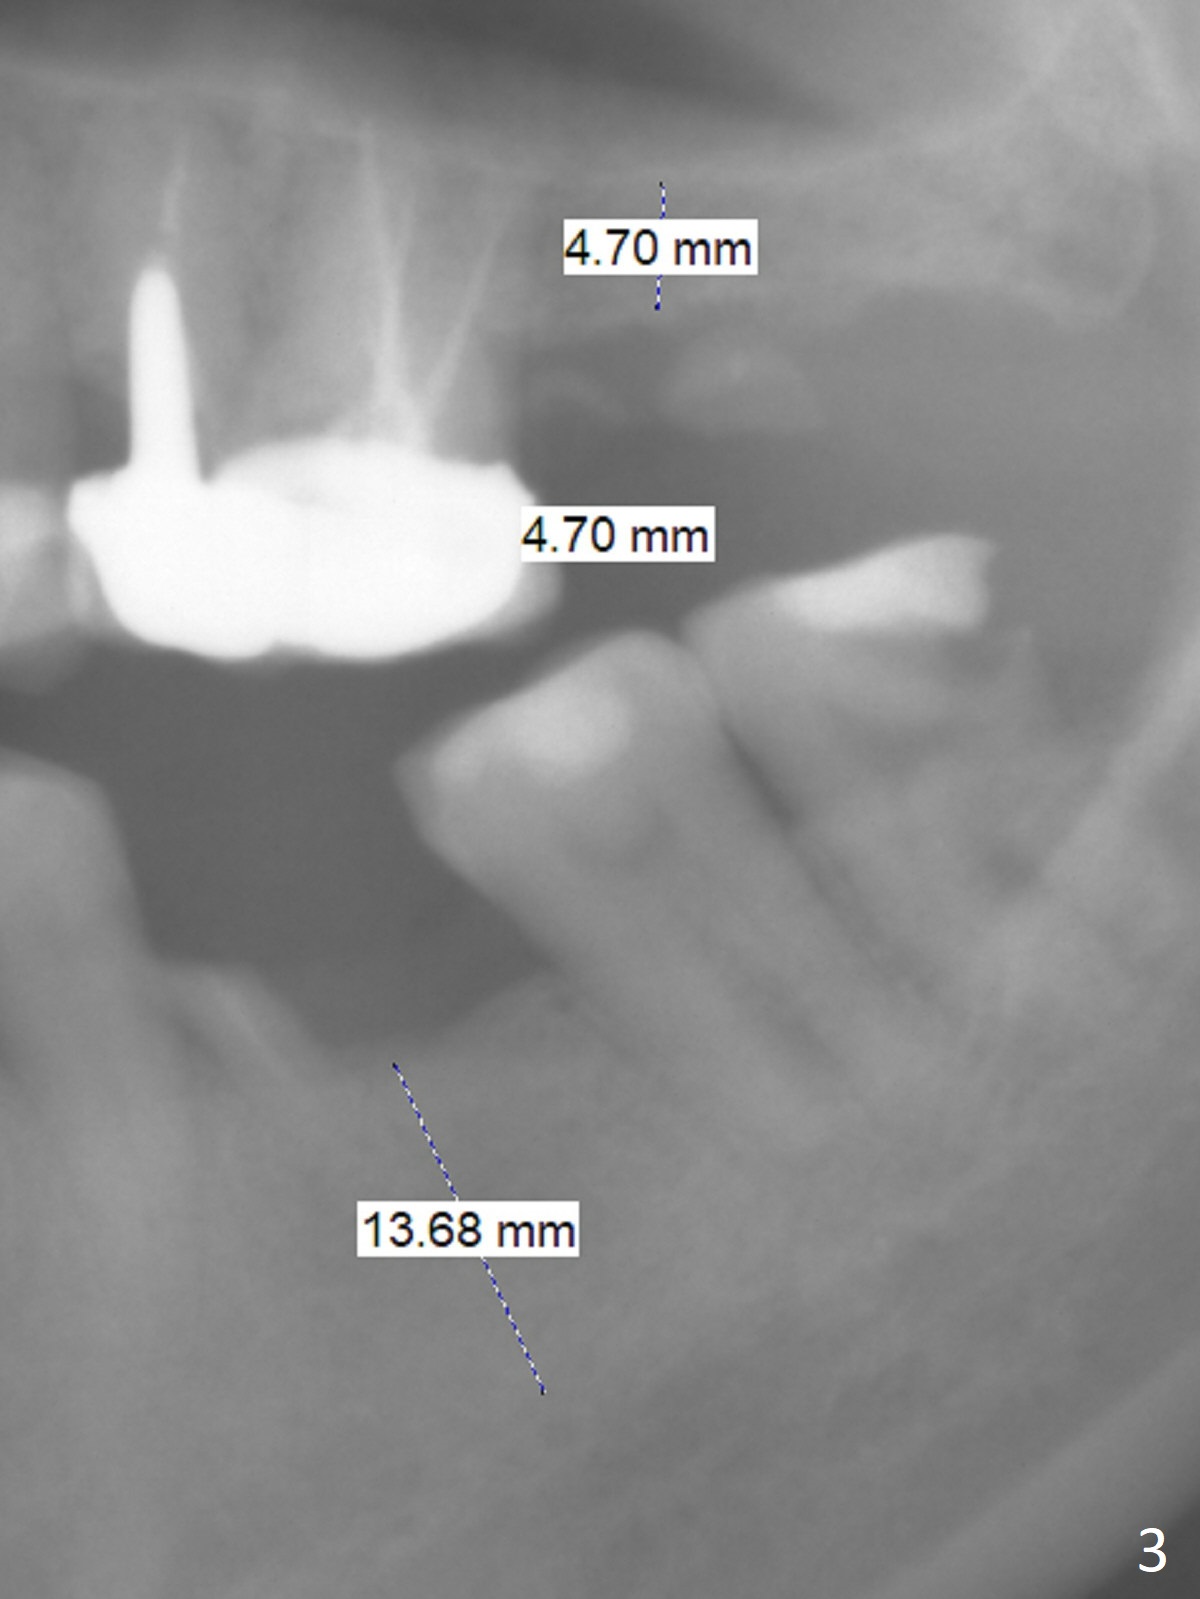

Bone Height Decreases As Residual Roots are Expelled M

A 47-year-old woman has residual roots at #15 and 19 (Fig.1). Seven years earlier, the bone height is ~ 7 mm (Fig.2), as compared to ~5 mm now (Fig.3). It is apparent that the bone height decreases as the residual roots are expelled. An advantage is that the ridge is flat, easy to initiate osteotomy. Magic Sinus Lifter is to be used for sinus lift. The regular surgical kit should be also available. Proximators will be used to remove the residual roots. Magic Split may be used to initiate osteotomy.

It is also easy to initiate osteotomy at #19 after removal of the mesial residual root (Fig.3). A 5x11 mm IBS implant will be placed (first as compared to #15). After extraction, use Magic Split to increase osteotomy site, followed by Magic Expanders and/or Drills. Take preop photos of the site to show the possible narrow ridge.